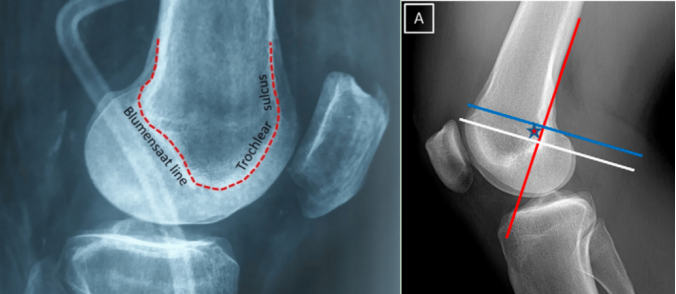

在临床上,基于患者的病史和膝关节体格检查来评估和确认髌骨不稳定情况。对每例患者都进行恐惧试验、髌骨倾斜度和髌骨轨迹检查。通过影像学检查测量髌骨高度、滑车发育不良情况、髌骨倾斜度、Q角以及胫骨结节 - 滑车沟(TT - TG)距离,以此来决定手术方案。拍摄下肢全长片以查看下肢力线。在处理复发性髌骨脱位时遵循特定的流程。

⑥然后,在透视下采用Schöttle技术,在导丝引导下于内收肌结节(AT)和股骨内上髁(MEC)中点前方的等长点处制作一个7毫米的骨隧道。等长点是在标准侧位平面上确定的,位于Blumensaat线后端点水平的近端、后皮质延长线前方1毫米处,以及股骨内侧髁后缘起点远端2.5毫米处。

在 2007 年的一项实验室研究中,Schottle 等人首次描述了 MPFL 重建过程中解剖股骨附着的可靠放射学标志。他们指出,在真正的侧位 X 光片上,解剖型 MPFL 股骨止点的放射学点位于股骨后皮层切线(参考线)前 1 毫米处,距离通过股骨内侧髁初始部分的垂直线远端 2.5 毫米,靠近通过 Blumensaat 线最后部追踪的垂直线的近端。